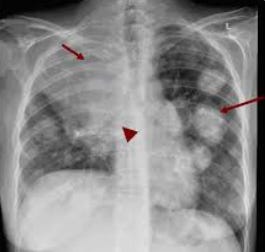

I am disturbed by the increasing failure of today's doctors, advanced practice providers, and nurses to deliver high-quality, competent, and error-free care. Here, I explore disturbing data trends.| Pierre Kory’s Medical Musings

In a three day span, I was told by four different patients of errors made by both physicians and nurses that harmed them, ranging from the catastrophic to the concerning.| pierrekorymedicalmusings.com